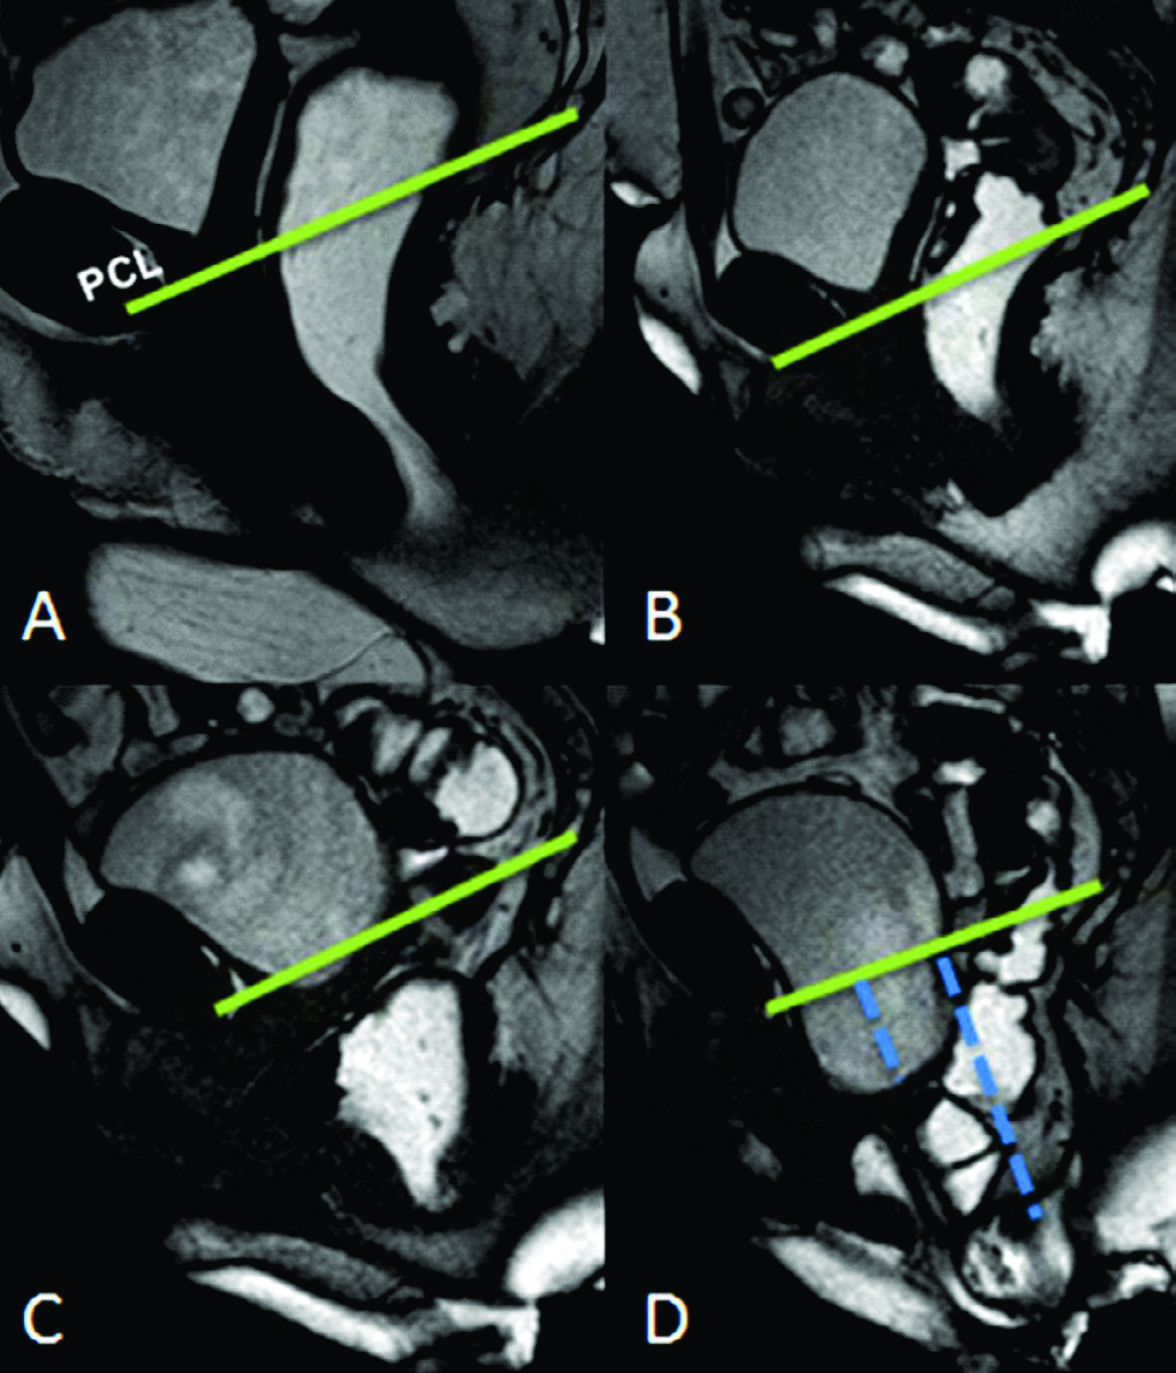

Figura 4

Línea H y línea M.Imágenes potenciadas en T2 de alta resolución en el plano sagital. Se observa el cambio en el valor que adopta la línea M y la línea H al comparar el reposo frente a la defecación. Según sus medidas en centímetros, se puede graduar en cuatro estadios diferentes.

Figura 9

Rectocele eversión

A) Imágenes potenciadas en T2 de alta resolución en el plano sagital a nivel de la línea media de una mujer durante el reposo.

B) TRUE FISP sagital durante maniobra de Valsalva.

C, D) TRUE FISP sagital durante defecación. El esfuerzo durante la defecación desciende el ángulo ano rectal y por lo tanto elonga la línea M y aumenta la línea H, que representa la apertura del hiato urogenital (B). Se evidencia cistocele (punteado verde en C), prolapso vaginal (estrella) y eversión del recto (flecha naranja).

Figura 10

C-D) TRUE FISP sagital durante defecación. Se evidencia cistocele, prolapso vaginal y eversión del recto. Las líneas punteadas azules cuantifican la severidad de los prolapsos.